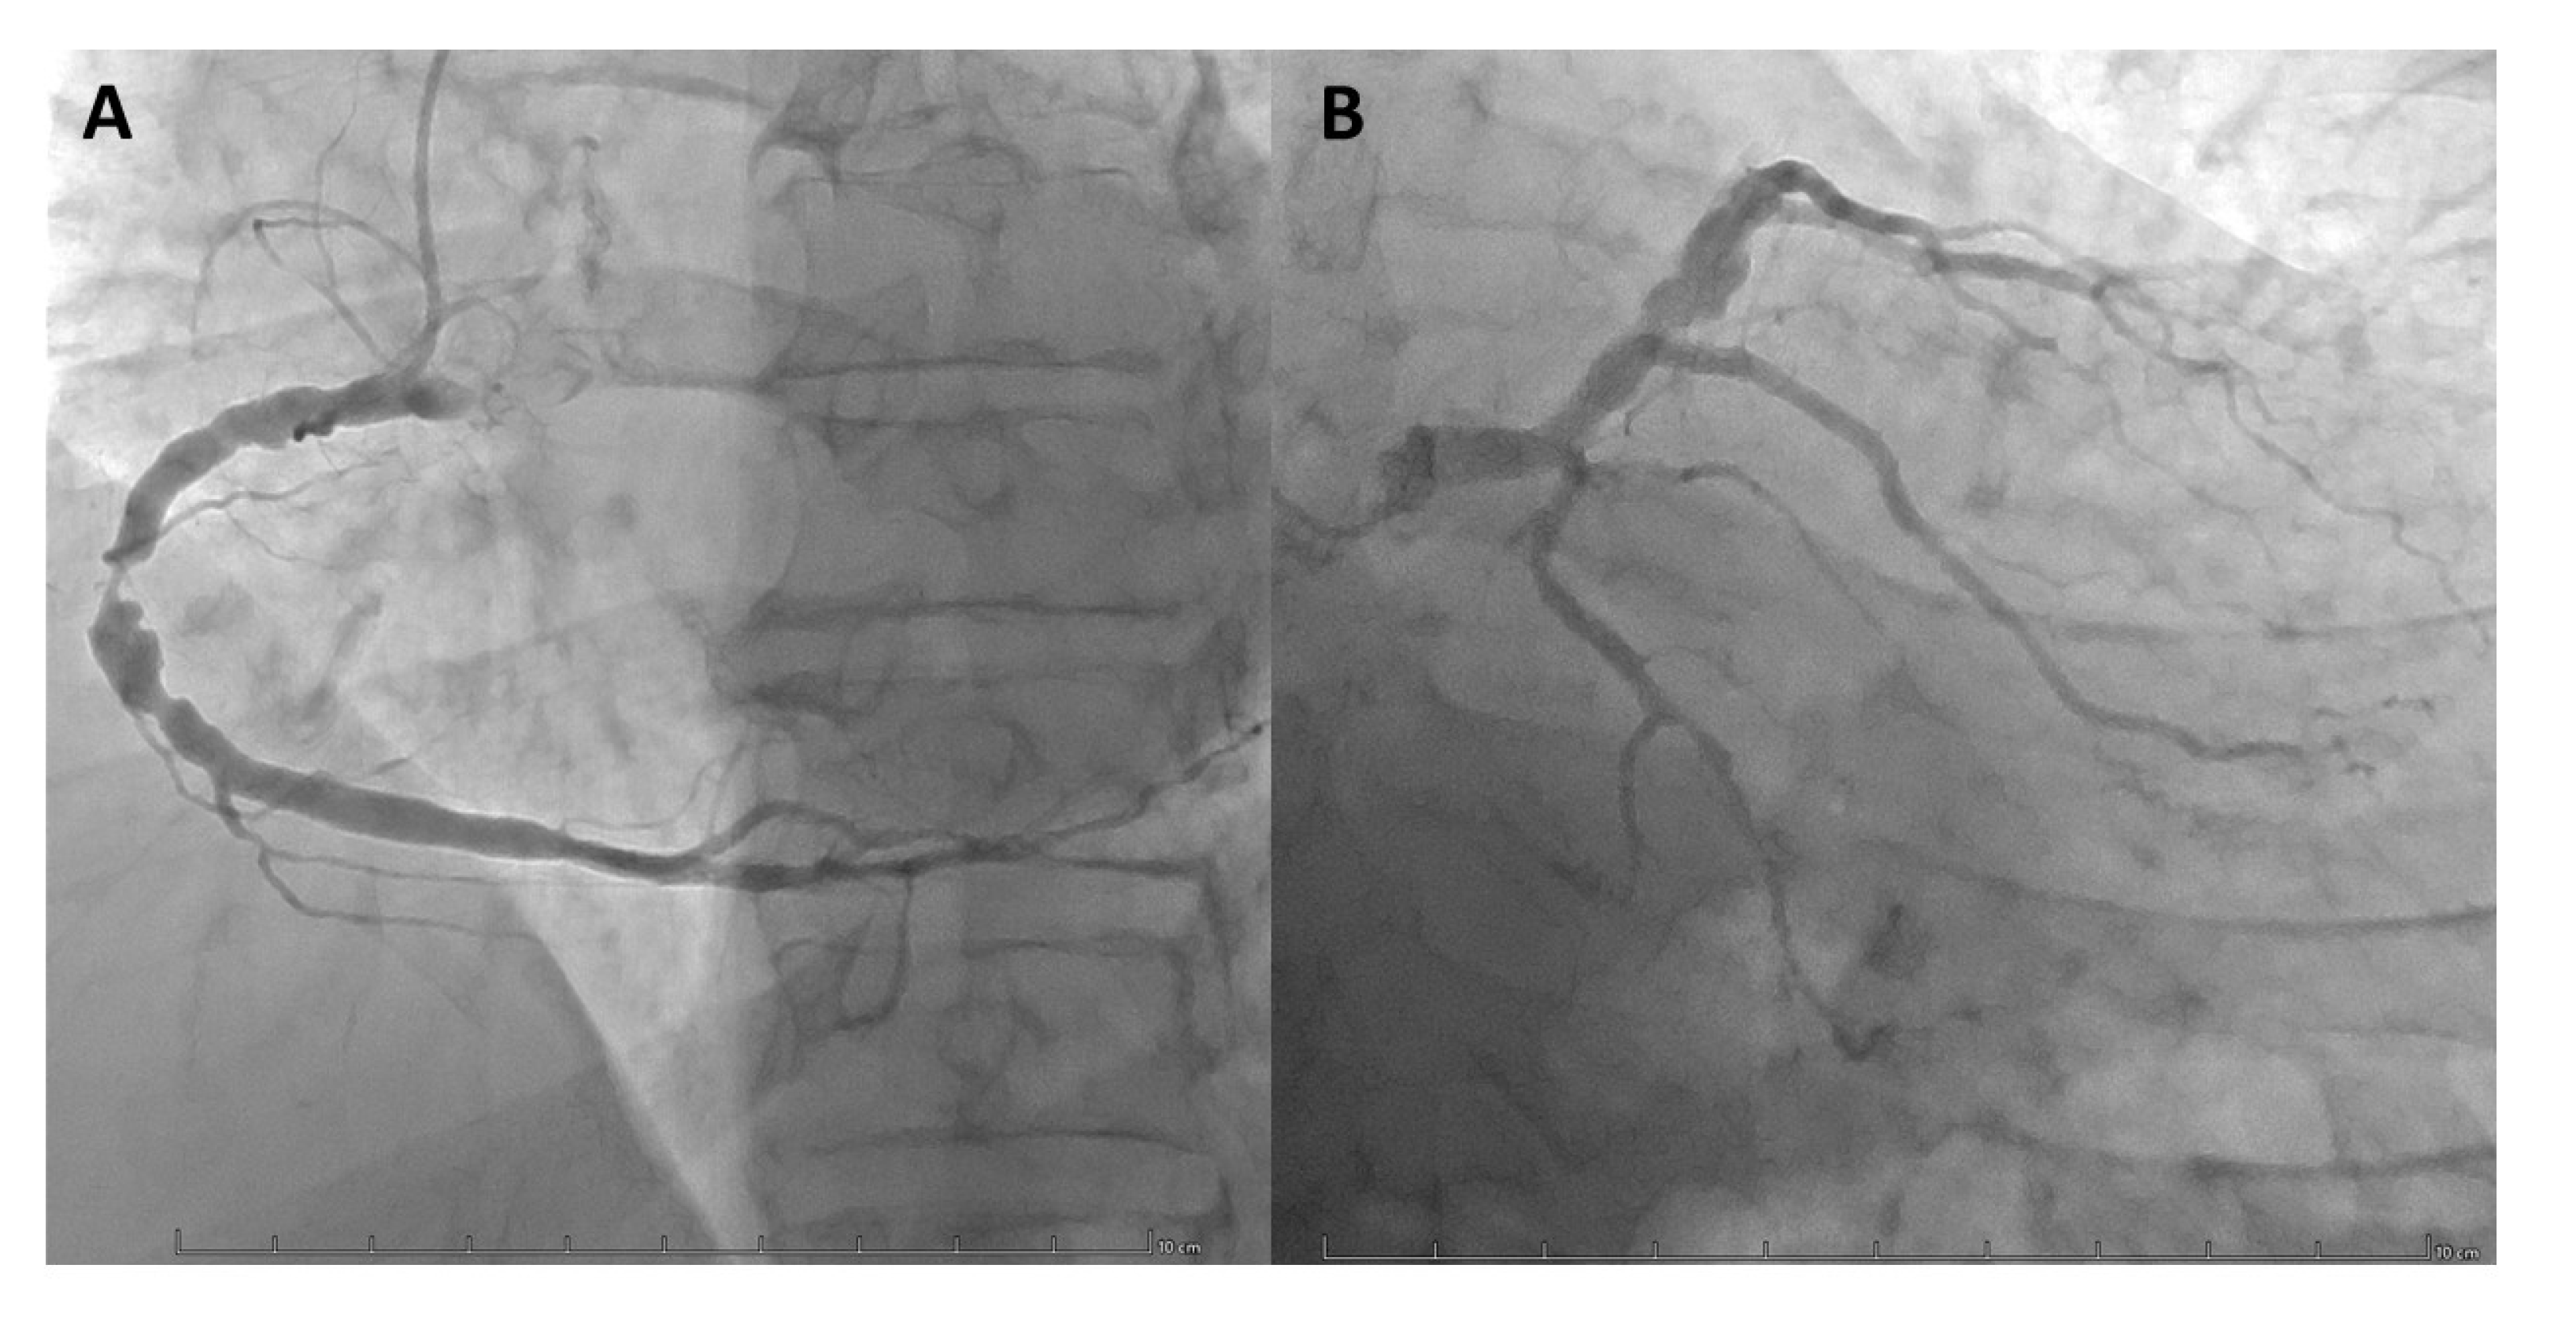

Figure 7. Coronarography images demonstrating focal coronary artery aneuryms localised on RCA (A) and LAD (B). Coronary aneurysms are defined as a focal dilatation of a coronary exceeding 1.5 times the diameter of the adjacent normal segment but involving less than 50% of the vessel length.

4.2.2. Coronary Artery Aneurysms

Coronary aneurysms are the second type of course anomaly that we will discuss. They are defined as a focal dilatation of a coronary exceeding 1.5 times the diameter of the adjacent normal segment but involving less than 50% of the vessel length (VS coronary artery ectasia that’s involve more than 50% of the vessel length). (Figure 7) There are two kinds of aneurysms: saccular and fusiform (these are most found in the LAD). The prevalence of these anomalies is of 1.4% in a population referred for coronary angiography. The pathophysiology leading to ischemia symptoms are poorly understood but the most common etiology is atherosclerosis in adults and Kawasaki disease in children. The presence of thrombi within the aneurysm lumen is frequent and can also lead to ischemic symptoms (14,23,29,30).

Treatment of coronary aneurysms is strongly individualized, taking into consideration multiple factors such as the presence of symptoms, etiology, expansion rate, location, size, and the presence of CAD to guide case-by-case decisions. There is an ongoing debate on anti-thrombotic therapy: although there's a potential risk of thromboembolism, the decision to use antithrombotic therapy remains controversial given the contradictory study findings, leading to a lack of consensus. Invasive treatment consists of PCI and surgery and is reserved for symptomatic patients. PCI is preferred for smaller aneurysms (58-10 mm in diameter) using covered stents or coil embolization, which is preferable for wide-neck aneurysms. Surgery is preferred for larger aneurysms (>10 mm) or patients with obstructive CAD, and the available surgical options include aneurysmectomy, marsupialization and complete ligation of the aneurysm with CABG, which is the most used technique. (29,39,49–51)